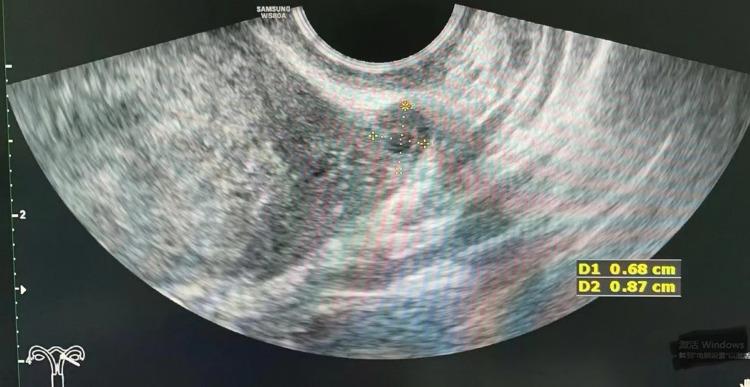

A 30-year-old gravida 1 para 0 woman with a history of left adnexectomy, due to left ovarian torsion 13 years ago, was referred to our hospital. She had experienced lower abdominal pain for 1 day and amenorrhea for 1 week. Transvaginal ultrasonography did not reveal an intrauterine pregnancy, but showed a suspected extrauterine gestational sac on the left adnexal area. The patient was diagnosed with ectopic pregnancy, and laparoscopy was performed. During the operation, we found a gestational sac on the left fallopian tube stump.

一名30岁、孕1产0的女性,13年前因左侧卵巢扭转行左侧附件切除术,现转诊至我院。她下腹痛1天,停经1周。经阴道超声检查未发现宫内妊娠,但在左侧附件区显示可疑宫外妊娠囊。患者被诊断为异位妊娠,并接受了腹腔镜检查。手术中,我们在左侧输卵管残端发现一个妊娠囊。